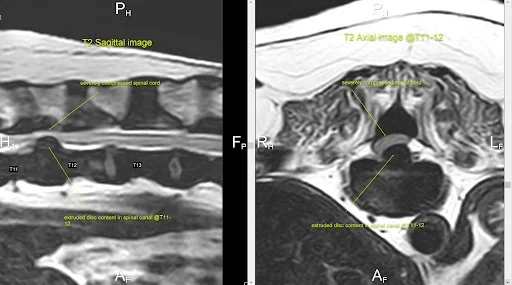

These images show a 13-year-old Dachshund with severe hind limb weakness that began after a traumatic jump. When medical management failed, surgery revealed a chronic disc extrusion causing marked spinal cord compression, explaining the profound weakness without complete paralysis. The patient began improving by the second postoperative day.

Sudden inability to walk in a Dachshund is most commonly caused by a disc herniation compressing the spinal cord. This can occur during normal activity and may progress rapidly. It is a medical emergency, and immediate veterinary evaluation greatly improves the chances of recovery.

These images are from an 11-year-old Dachshund that developed significant hind limb weakness two days after the onset of back pain. The disc material appears less hypointense (lighter), consistent with an acute extrusion that was easily removed at surgery. The patient made a full recovery.